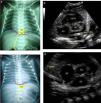

A figura 1 mostra dois exemplos de discordância entre as avaliações da posição do CVU pela radiografia anteroposterior de tórax e a imagem ecocardiográfica correspondente.

Radiografia anteroposterior de tórax que mostra o cateter venoso umbilical em T9, logo acima do diafragma e na junção cavoatrial, interpretado como bem posicionado (a) e imagem ecocardiográfica correspondente (b) que demostra a extremidade distal do cateter no átrio esquerdo, após atravessar o septo interatrial (*). Em outro recém‐nascido, a radiografia mostrou o cateter entre T9 e T10, abaixo do diafragma e da junção cavoatrial, o que sugere posicionamento no fígado (c), porém sua extremidade foi identificada corretamente na junção da veia cava inferior com o átrio direito pela ecocardiografia (d). AD, átrio direito; AE, átrio esquerdo; AO aorta; CVU, cateter venoso umbilical; VSVD, via de saída do ventrículo direito.